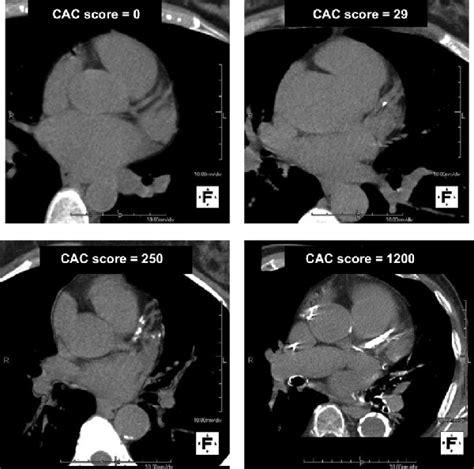

High Calcium Score Ct Scan. The absolute agatston score and the age, sex,. Web a calcium score test is a ct (computed tomography) scan that looks at how much calcium is in your coronary arteries.

You and your doctor can take the. Web the coronary calcium scan tells you how much calcified plaque is in your heart’s arteries. Web a calcium score test is a ct (computed tomography) scan that looks at how much calcium is in your coronary arteries. Web important points to report when interpreting cac scans include: The absolute agatston score and the age, sex,.